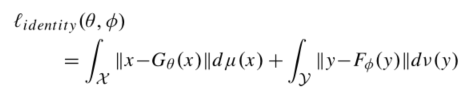

另外考虑到,在实际应用中我们可能把 x 输入Gtheta 这种将输入颠倒的情况,所以该篇文章添加了身份认证损失,当我们将x输入Gtheta时,输出还是x. 可以用以下认证损失表示: